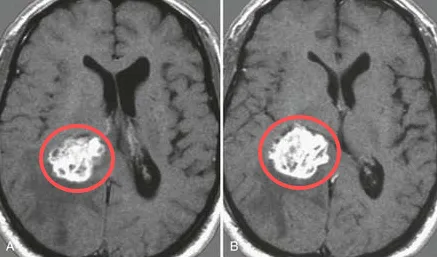

INC魯特卡教授也曾為一名脈絡(luò)叢乳頭狀瘤患兒進行手術(shù)——磁共振成像(MRI)顯示,奧利佛右側(cè)腦室后角有一個大腫塊,考慮脈絡(luò)叢乳頭狀瘤病變,并有蒂連接,伴有中度腦積水。

脈絡(luò)叢乳頭狀瘤

魯特卡教授通過右頂骨開顱手術(shù)和側(cè)腦室切開后中央回后方的皮質(zhì)切口。暴露血管高度豐富的腫瘤,逐塊切除腫瘤。

經(jīng)過魯特卡教授的手術(shù)治療,奧利佛康復(fù)得十分順利。兩周后,奧利佛的所有體征和癥狀術(shù)后均已緩解。CT掃描結(jié)果顯示,腦積水減少,脈絡(luò)叢正常。他平安出院,術(shù)后也無需任何輔助治療。